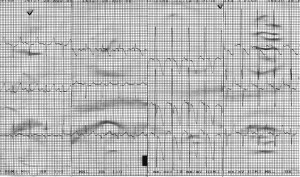

Evoluţia imediat postoperatorie a fost fără complicaţii, sugarul revenind în secţia de cardiologie pentru recuperare. Condiţiile generale erau ameliorate, notându-se chiar şi o uşoară creştere ponderală. Controalele ecocardiografice succesive au evidenţiat însă o dilataţie graduală a ventriculului stâng cu afectarea progresivă a funcţiei sistolice şi apariţia ulterioară a unei insuficienţe mitrale severe. Nu a putut fi vizualizată originea arterei coronare stângi din aortă, în plus notându-se flux bidirecţional în artera coronară descendentă anterioară la examenul Doppler color, ridicând suspiciunea de origine anormală a arterei coronare stângi (Figura 3). Presiunea pulmonară se redusese semnificativ (presiunea pulmonară medie a scăzut de la 40 mmHg la 21 mmHg), iar la nivelul septului interatrial nu exista şunt rezidual. Electrocardiograma evidenţia semne de ischemie miocardică, inexistente pe electrocardiogramele de dinainte de intervenţie: segment ST subdenivelat descendent în precordialele stângi şi unde T negative simetrice în precordialele drepte (Figura 4).

Figura 4. Electrocardiogramă: segment ST subdenivelat descendent în precordialele stângi şi unde T negative simetrice în precordialele drepte.